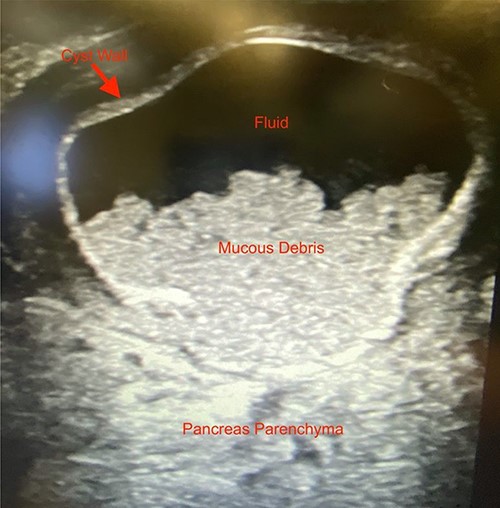

We noted that the patient had an annular pancreas; there was pancreatic tissue around D2 with no evidence of stenosis. There were dense adhesions between the posterior wall of the stomach and this mass, which was essentially embedded within the head of the pancreas and closely positioned but separate from the medial wall of D1 and posterior stomach. There was scarred inflammation extending along the transverse mesocolon, but no true fistula was seen (Fig. 2). There was no evidence of a connection to the pancreatic duct. An intraoperative ultrasound revealed a thick-walled cyst; the fluid in the cyst was of low density with areas of mucous debris dependently (Fig. 3).

Intraoperative ultrasound image revealing a thick-walled mass intimately associated with the pancreas filled with fluid and mucous debris.